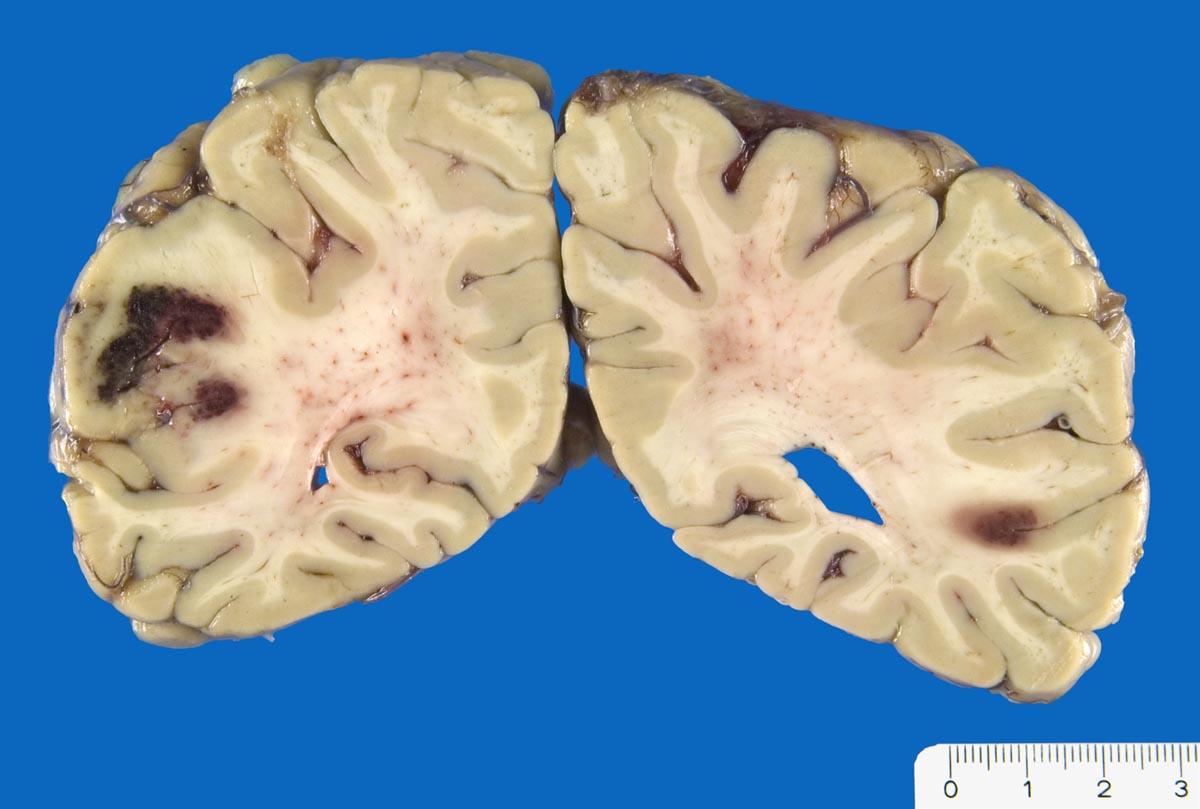

• Frische Nekrose und Demarkation (0-5 Tage): Makroskopisch nach 12 Stunden leichte Erhabenheit erkennbar (Ödem). Erweichung. Unscharfe Mark-Rindengrenze. Mikroskopisch eosinophile Degeneration der Neurone und ödematöser Randsaum.

• Resorption und Abräumung (ab 5. Tag, vorliegender Fall): Mit zunehmendem Alter des Infarktes wird das Gewebe weicher und zerfällt innerhalb einiger Wochen zerfliessend kleinzystisch (Kolliquationsnekrose). Mikroskopisch ab dem zweiten Tag Auftreten von Makrophagen im Randbereich. Durch Phagozytose von Myelinbruchstücken lipidhaltige Vakuolen im Zytoplasma der Makrophagen (=Fettkörnchenzellen). Nervenzellen im Randbereich der Nekrose können das Bild einer ischämischen Schädigung zeigen (Hypereosinophilie). Gefässproliferation. Perifokale Gliose.

• Organisation und Zystenbildung (ab 1-8 Wochen): Übergänge zum Stadium 2 sind fliessend. Vermehrung von Fettkörnchenzellen rund um proliferierte Kapillaren. Endstadium des anämischen Infarktes bildet ein zystischer Parenchymdefekt, im Gegensatz zu anderen Organen (Herz, Niere) findet kein narbiger Umbau statt. Die in der deutschsprachigen Literatur oft erwähnte "Hirnnarbe" bezieht sich auf die reaktive Gliose im Randbereich des Infarktes. Eine reaktive Gliose ist unspezifisch und findet sich in der Nachbarschaft verschiedener Läsionen (beispielsweise Blutungen, Tumoren, Abszesse etc.). Alte abgebaute Infarkte sollen makroskopisch von alten Kontusionsherden abgegrenzt werden. Diese befinden sich praktisch ausschliesslich in frontobasaler oder temporobasaler Lokalisation (> 1436), wo umschriebene Hirninfarkte nicht vorkommen.

• Links unten leptomeningeale Gefässe mit partiell rekanalisierten alten thromboembolischen Verschlüssen.

• Unscharfe Mark-Rindengrenze im Bereich der nekrotischen Rinde.

• Spongiotische Auflockerung der Hirnrinde (hellere Areale).